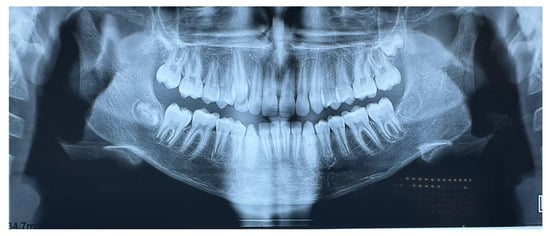

Extraoral clinical examination revealed a convex facial profile (Figure 2). Intraorally, the subject exhibited a Class II Division I type malocclusion with a bilateral Class II molar and canine relationship and an overjet of 9 mm. The maxillary incisors were proclined and, with the exception of a maxillary permanent canine, all permanent teeth were present in both arches, as shown in OPT (Figure 3).

The extraoral image shows the convex profile, while the intraoral images show the Class II molar and canine relationship and the protrusion of the upper incisors with the presence of diastemas.

Figure 3.

Orthopantomography at T0.